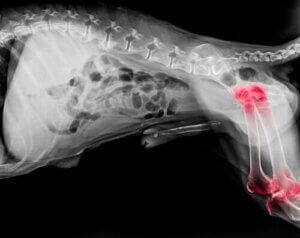

Arthritis bei Hunden

Schätzungsweise leidet etwa jeder fünfte Hund an Arthritis. Obwohl diese Gelenkerkrankung in jedem Alter auftreten kann, sind ältere Hunde am ehesten davon betroffen.

Im Allgemeinen ist Arthritis eine degenerative Erkrankung, die eine Entzündung der Gelenke sowohl in den Ellenbogen als auch in den Knien verursacht.